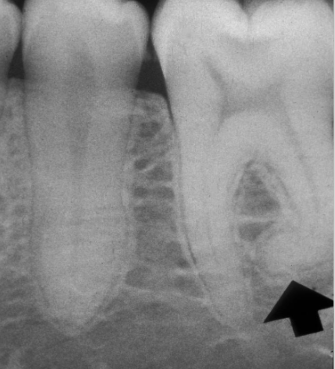

DGI radiographic presentation

bulbous crown, cervical constriction, pulp obliteration varies, expanded pulp = shell teeth

dentin dysplasia (DD)

radicular dentin dysplasia

4 types, normal clinical crown, short roots, periapical radiolucencies, chevron pulp chambers

DD-I